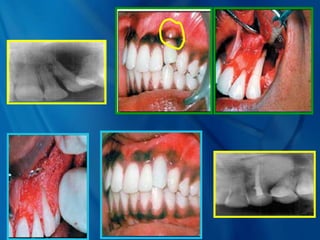

• This fistula on the labial

surface looks like an

endodontic abscess.

• Diagnosis of any abscess

must include periodontal

probing, periapical

radiographs ,vitality tests and

a patient history .

This case shows a

combination of periodontitis

and endodontic

inflammation

causing bone loss at the

crest and at the apex.